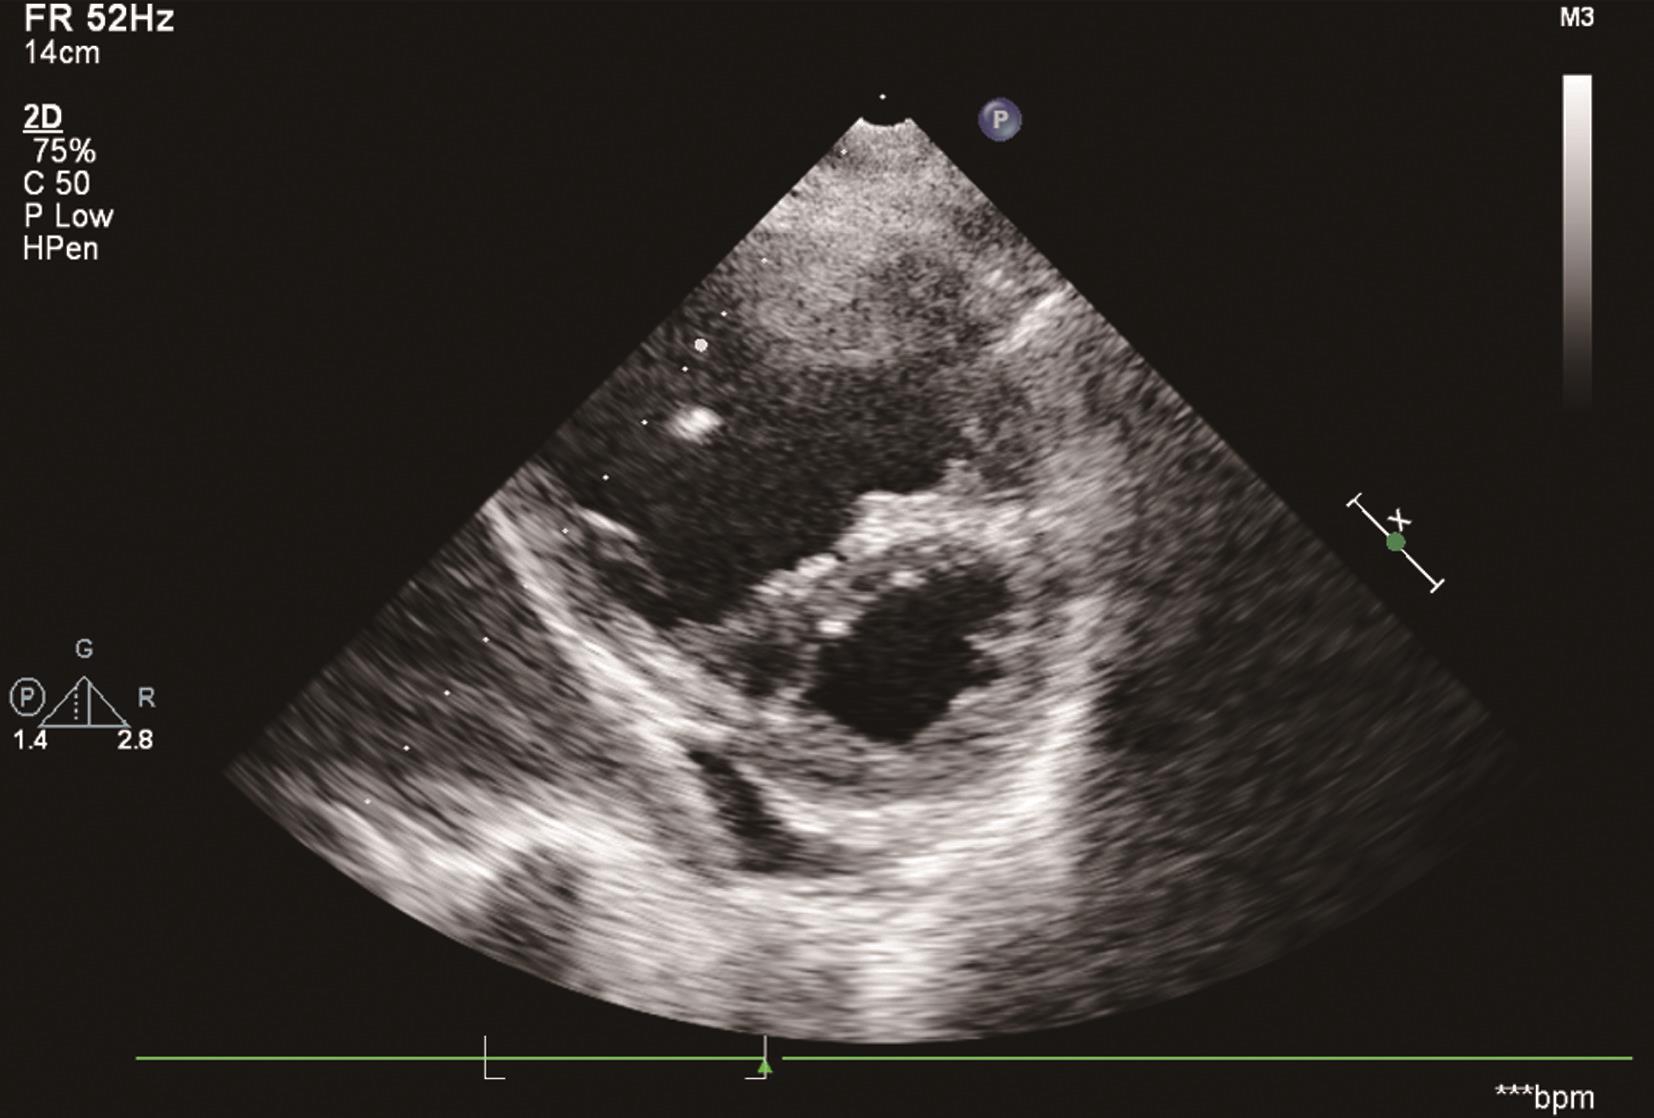

1.直接征象为显示出右心、肺动脉及其左右分支主干内有血栓。①主肺动脉和左右肺动脉内径增宽,探及不规则团块状血栓回声(图6-1-1),多附着于血管壁,以左肺动脉血栓栓塞发病率高,相应肺动脉内团块附着处血流信号消失,其周围流通部分血流流速加快;②右心内探及血栓回声合并右心扩大、肺动脉高压者可直接诊断肺栓塞。此外,上、下腔静脉,肝静脉、门脉系统血栓形成伴有右心室扩大或肺动脉高压也可视为直接征象。

图6-1-1 主肺动脉和左右肺动脉内径增宽,探及团块状血栓回声